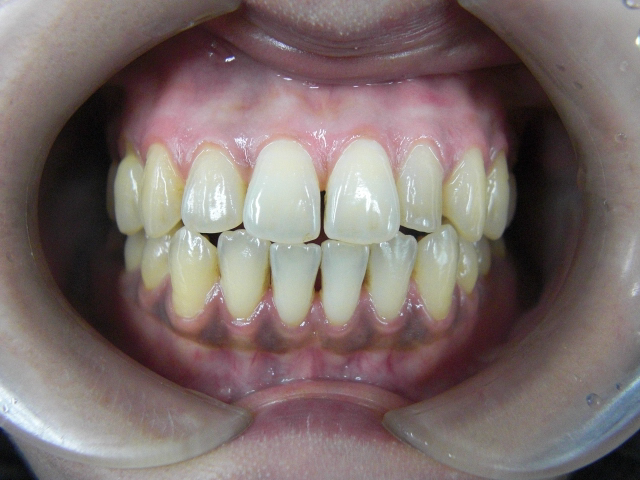

↑ 初診時のお写真です。

はぐきの上下ともに黒くなっています。

30歳代、喫煙習慣がある方です。